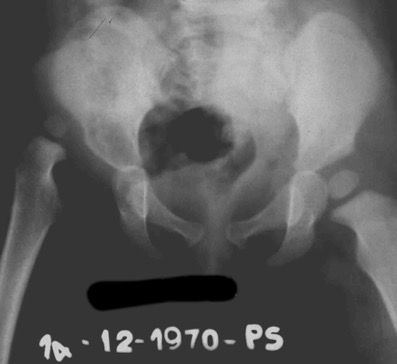

Lussazione dell'anca destra In questo articolo affrontiamo il caso di una piccola paziente affetta la lussazione vera dell’anca dx.

Posta in trazione allo zenit il femore scendeva gradualmente verso l’acetabolo.

Una volta raggiunta l’altezza dell’acetabolo, la paziente veniva operata (Istituto Rizzoli) e ridotta . La paziente veniva ingessata in apparecchio femoropodalico

E successivamente mantenuta in divaricatore di Putti x diversi mesi. Come si può osservare dalla radiografia la testa del femore dx non solo è di ridotte dimensioni ma ha subito una crisi vascolare, come si vede dalla parte mancante. Questo fenomenoo denominato osteocondrite post-riduttiva è dovuto a una crisi vascolare dell’irrorazione della testa femorale